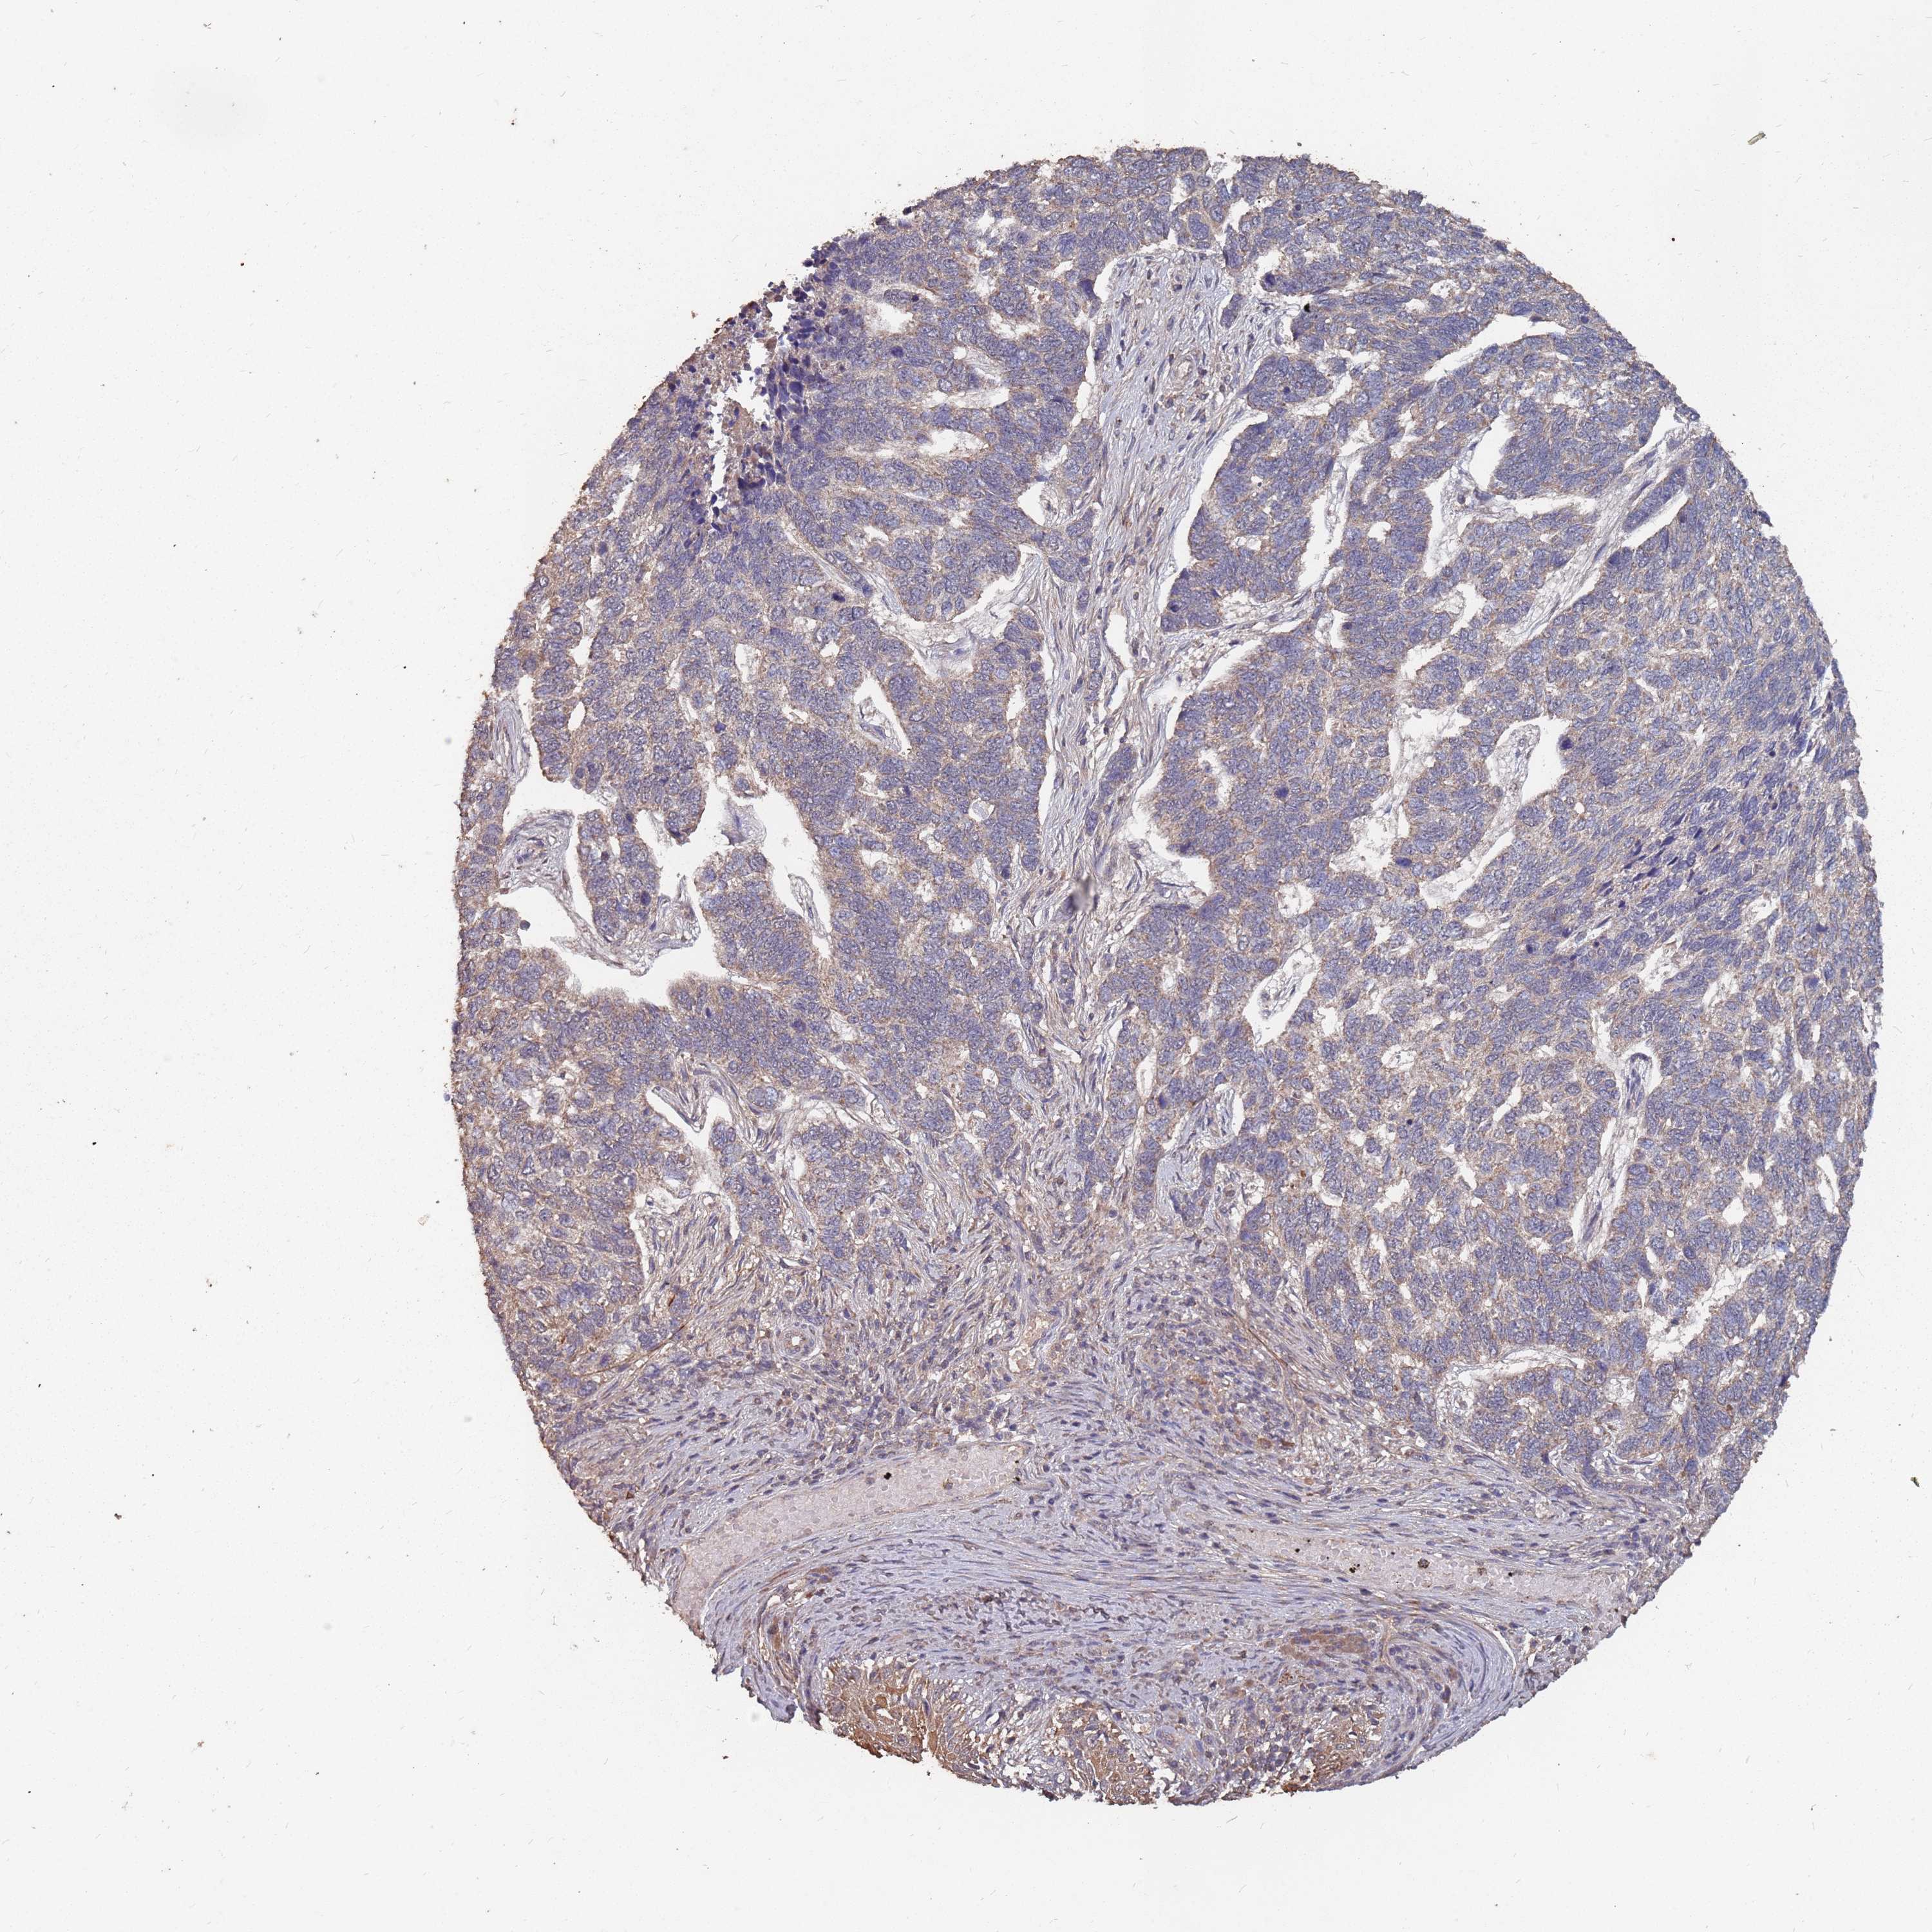

SKIN CANCER - Protein expressioni

A mouse-over function shows sample information and annotation data. Click on an image to view it in a full screen mode. Samples can be filtered based on level of antibody staining by selecting one or several of the following categories: high, medium, low and not detected. The assay and annotation is described here.

Antibody stainingi

Antibody staining in the annotated cell types in the current human tissue is reported as not detected, low, medium, or high, based on conventional immunohistochemistry profiling in selected tissues. This score is based on the combination of the staining intensity and fraction of stained cells.

Each image is clickable and will lead to virtual microscopy that enables deeper exploration of all samples and also displays staining intensity scores, fraction scores and subcellular localization as well as patient and tissue information for each sample.

Antibody HPA020459

Basal cell carcinoma

Squamous cell carcinoma, NOS

Squamous cell carcinoma, metastatic, NOS